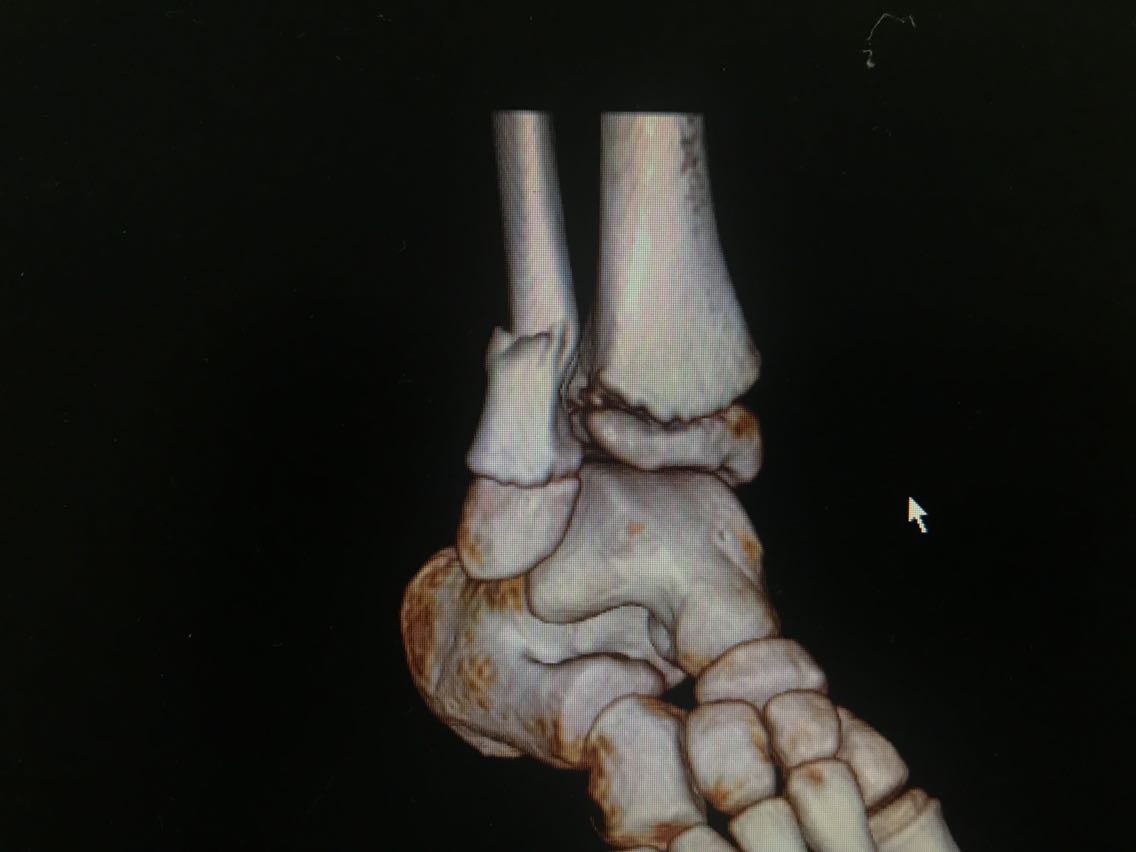

患者男性,10岁。 主诉:摔伤致右小腿疼痛,活动受限3+天 现病史:患者3+天前从高处摔下,高度约6米,摔下后右足着地。患者自述右侧小腿下段疼痛,可以耐受,意识清楚,呼之能应,无呕吐其他不适。右小腿肿胀、疼痛伴活动障碍,局部皮肤有明显青紫,无破损、流血等。遂至当地医院就诊,未予特殊处理,建议上级医院就诊。遂就诊于我院急诊科,行X线检查示:右侧腓骨下段骨折,断端稍成角、迂曲,右外踝关节间隙稍增宽,周围软组织肿胀。CT检查示:右侧腓骨下段骨折,断端稍成角、迂曲,右外踝关节间隙稍增宽,右胫骨干骺端与骺板间隙稍增宽,周围软组织肿胀。经我科医师会诊,以“右腓骨下段骨折”收入我科。患者自受伤以来精神睡眠可,食欲可,大小便正常,体重未见明显变化。 既往史无特殊。

查体:右小腿远端、足部肿胀明显,局部皮肤可见青紫,未见破损,右小腿远端皮温低,压痛不明显,桡动脉、足背动脉搏动可,右踝节活动受限,右足趾感觉、血运、活动正常,其余肢体未见明显异常。 辅助检查: X线检查,示:右侧腓骨下段骨折,断端稍成角、迂曲,右外踝关节间隙稍增宽,周围软组织肿胀。请结合临床及其它检查。右侧胫骨未见确切错位骨折征象。 CT检查,示:右侧腓骨下段骨折,断端稍成角、迂曲,右外踝关节间隙稍增宽,右胫骨干骺端与骺板间隙稍增宽,周围软组织肿胀。请结合临床及其它检查。